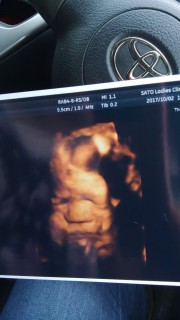

32w2d1705gの男の子です! 今日はとても綺麗に撮れたと先生にも看護師さんにも誉めて頂きました(´∀`) 丸い鼻は私似かな?笑 早く会いたいよー※。.:*:・'°☆